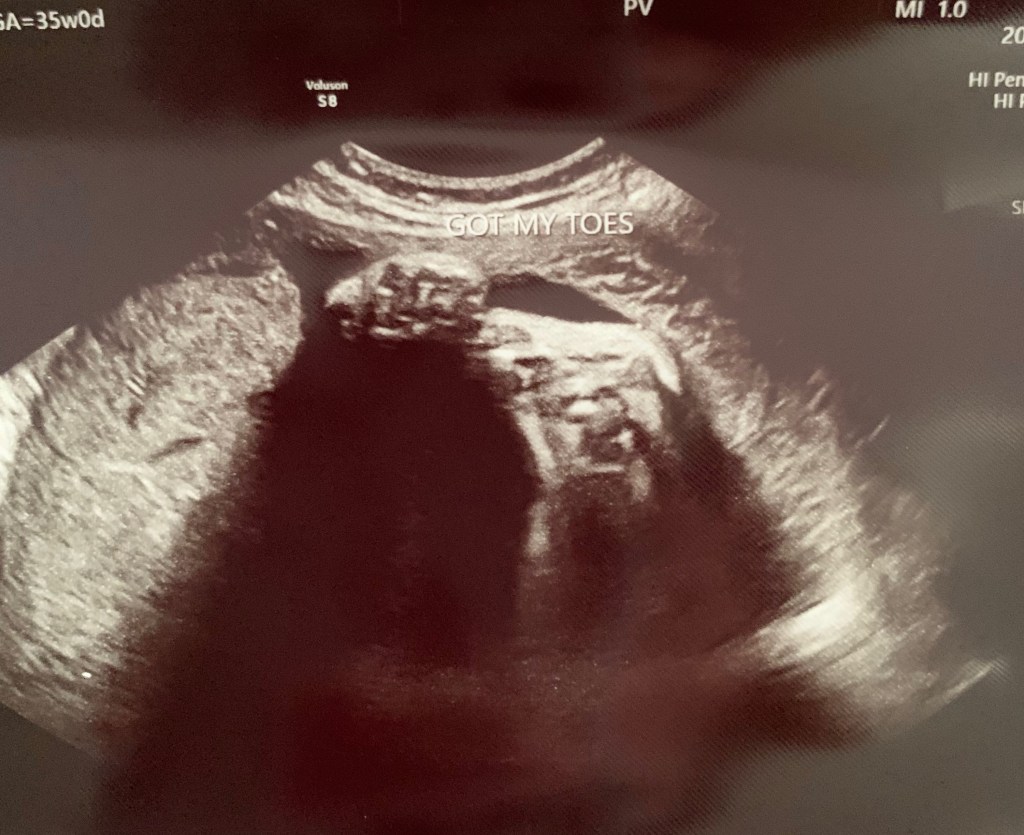

Hand grabbing their toes